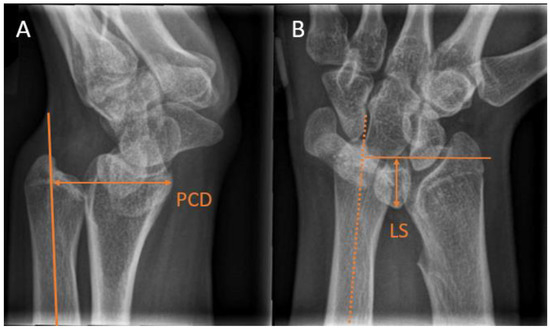

Madelung deformity is a rare congenital arm condition that affects the growth plate of the distal radius. The lagging growth of the distal radius results in a radioulnar and radiocarpal misalignment. The progressive growth disturbance may eventually lead to a three-dimensional wrist deformity [40]. Madelung deformity is usually diagnosed between the ages of 6 and 13 years [41]. In children with Madelung deformity, additional ulnar radiological measurements are indicated. Farr et al. [40] stated that in addition to ulnar variance, a lunate subsidence (LS) >4 mm and a palmar carpal displacement (PCD) >20 mm were radiographic criteria for undergoing an ulnar shortening osteotomy. They measured PCD on a lateral radiograph as the distance between the longitudinal ulna axis and the most volar aspect of the lunate (Figure 6A). LS was measured on a PA radiograph as the distance between a perpendicular line to the longitudinal ulna axis and the most proximal point of the lunate. (Figure 6B). Symptoms of Madelung deformity can range from wrist pain to decreased function. Most commonly, patients experience a limited range of motion in the wrist and continuous or post-activity wrist pain.

Figure 6. Radiographic wrist measurements used for the assessment of Madelung deformity. (A) Palmar carpal displacement (PCD) on a lateral wrist view, measured as the distance between the longitudinal ulna axis and the most volar lunate aspect. (B) Lunate subsidence (LS) on a posterioanterior view, measured as the distance between a perpendicular line to the longitudinal ulna axis and the most proximal lunate point.